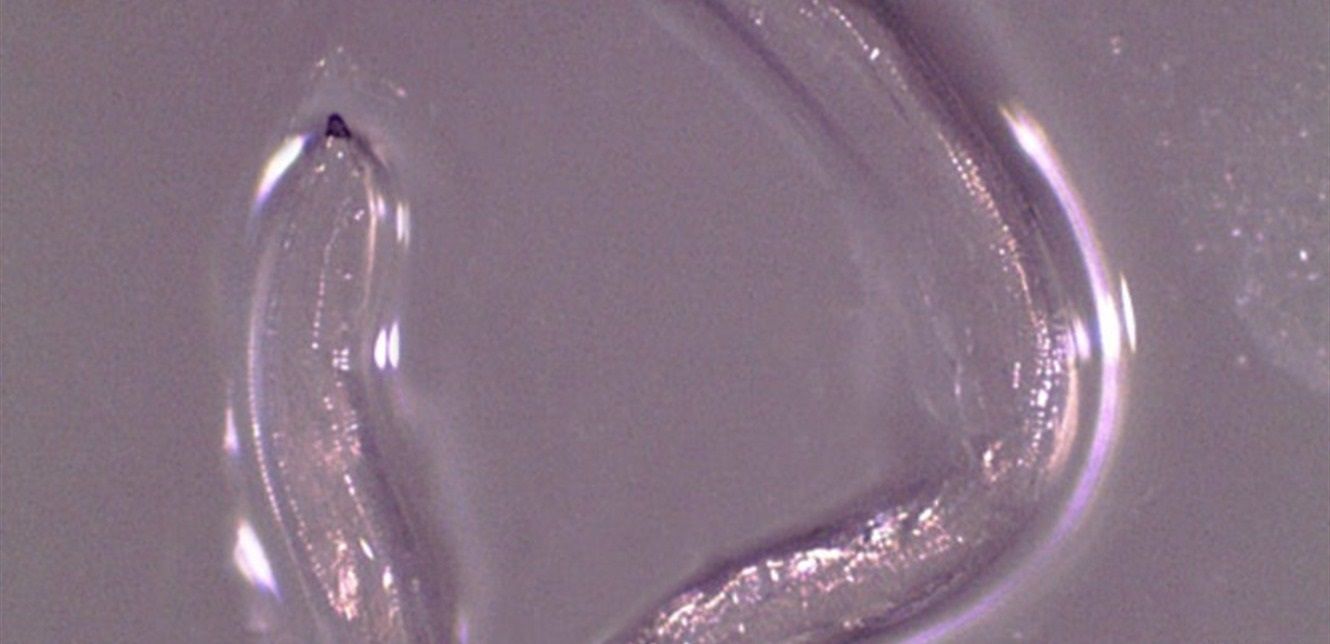

وعانت المرأة من تهيج في عينيها لمدة أسبوع بعد ركوبها الخيل في مكان لتربية الماشية. وبعد طلب المساعدة الطبية تمت إزالة 14 دودة تسمى Thelazia gulosa يبلغ طول كل منها حوالي سنتيمتر.